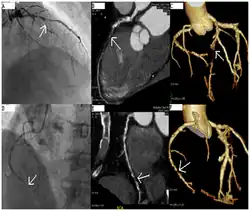

A coronary angiogram (an X-ray with radiocontrast agent in the coronary arteries) that shows the left coronary circulation. The distal left main coronary artery (LMCA) is in the left upper quadrant of the image. Its main branches (also visible) are the left circumflex artery (LCX), which courses top-to-bottom initially and then toward the centre/bottom, and the left anterior descending (LAD) artery, which courses from left-to-right on the image and then down the middle of the image to project underneath the distal LCX. The LAD, as is usual, has two large diagonal branches, which arise at the centre-top of the image and course toward the centre/right of the image.

Coronary angiography of a critical sub-occlusion of the common trunk of the left coronary artery and the circumflex artery. (See arrows)

Angiography (left) and CT (middle and right) of chronic total occlusion lesions at the left anterior descending coronary artery (LAD) and right coronary artery (RCA).